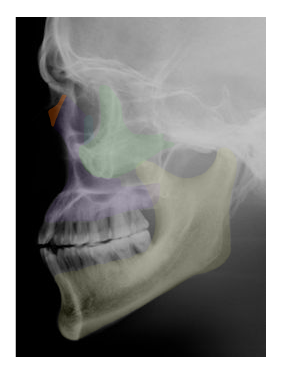

Cranial and Facial Bones

Students will use images and descriptions to reinforce their knowledge of the cranial and facial bones.

in orange,  | NASAL |

in purple,  | TEMPORAL |